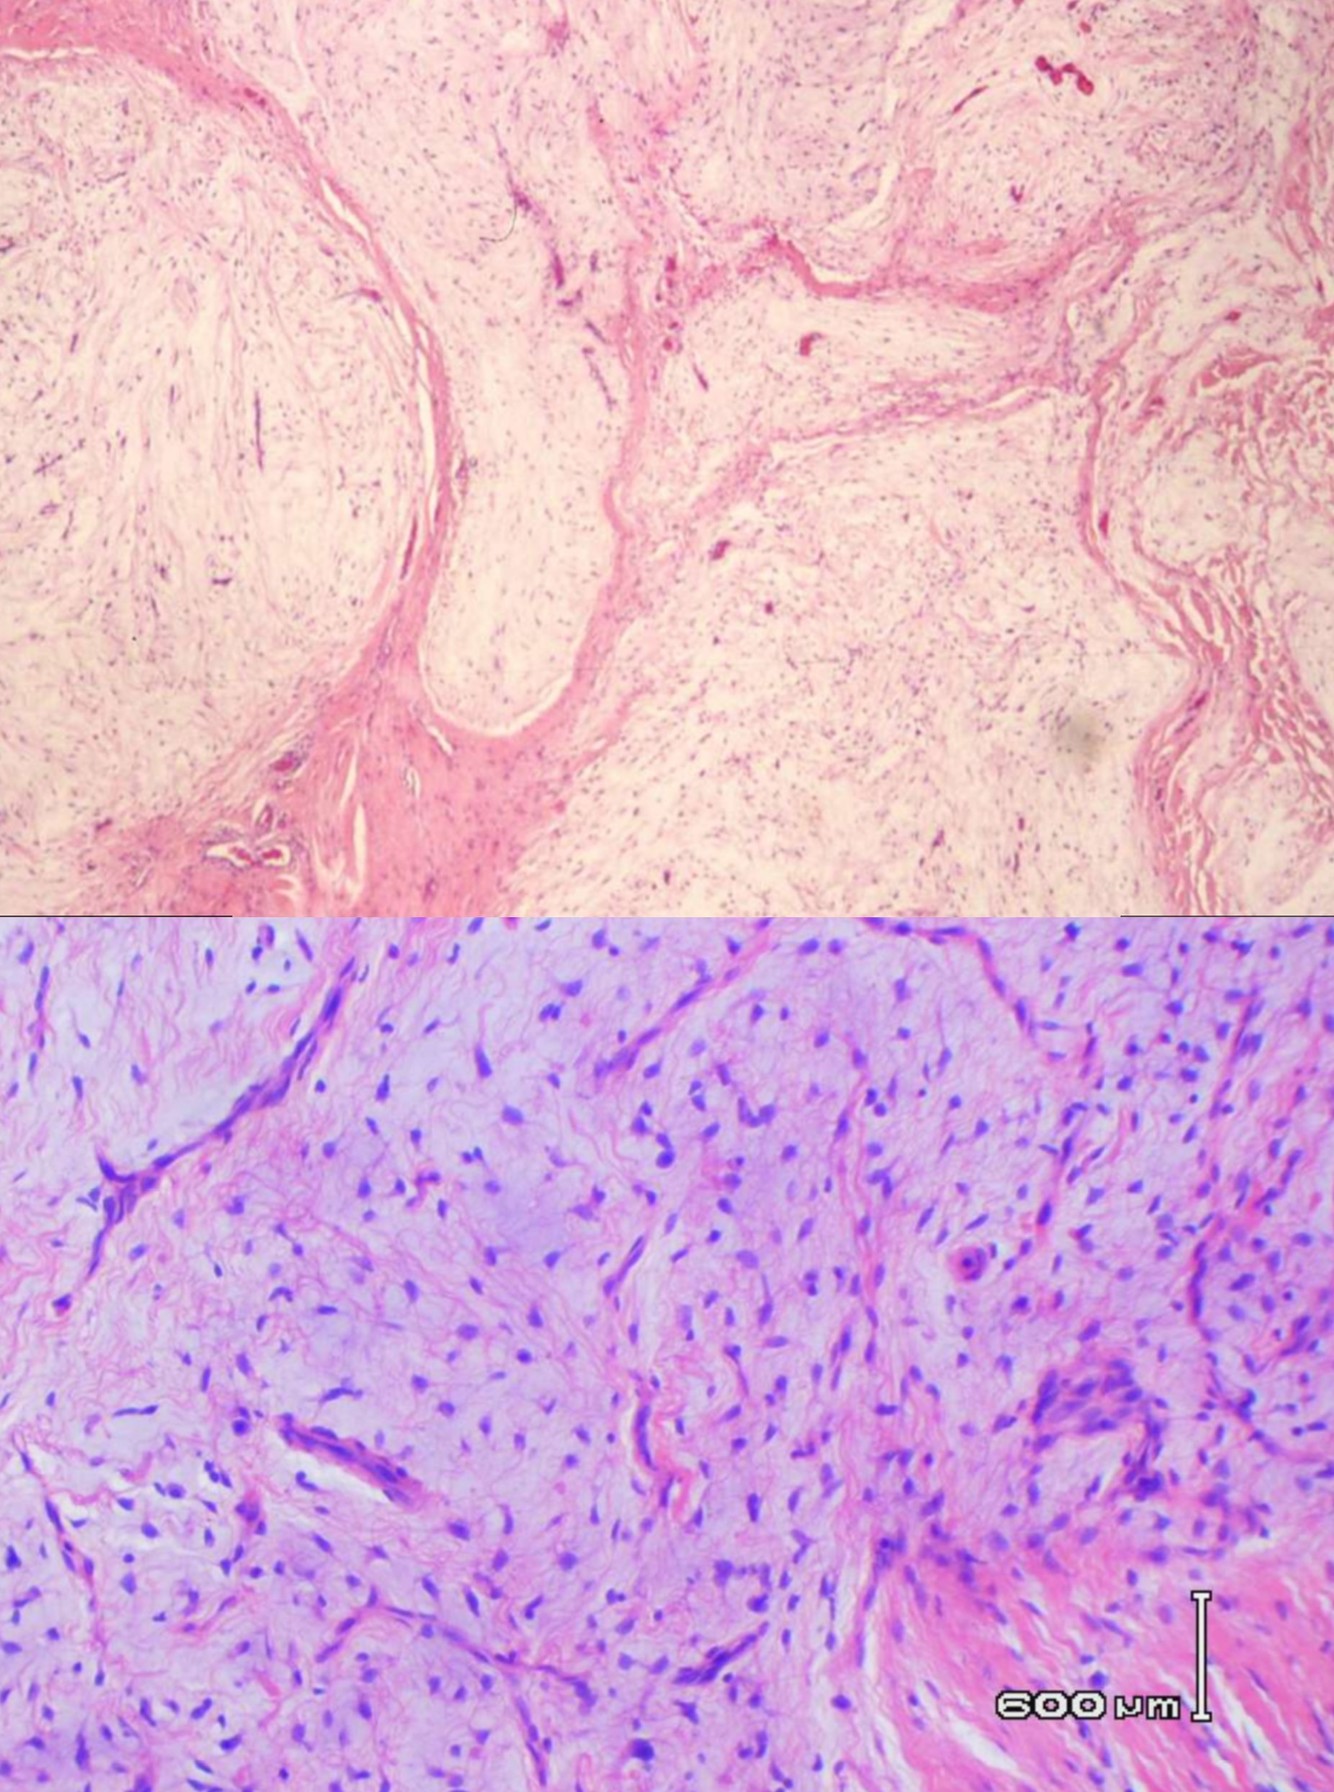

Dermatofibrosarcoma Protuberans * slow-growing dermal spindle cell tumor of intermediate malignancy * typically occurs on the trunk and proximal extremities of young and middle-aged adults * solitary lesion or multiple polypoid nodules arising in an indurated plaque * Local recurrence is common, occurring in one third of all cases. * immunohistochemical and ultrastructural evidence indicates a fibroblastic origin * t(17;22) translocation in \> 90% --\> pathogenic COL1A1-PDGFB fusion gene * most helpful diagnostic marker is CD34, which stains 50% to 100% of the cells * CD34 is negative or focally positive in dermatofibromas * PCR may be used to identify the COL1A1-PDGFB fusion gene DDx: Giant cell fibroblastoma * considered a variant of dermatofibrosarcoma protuberans that often manifests in childhood * may exhibit the same immunogenetic and cytogenetic profile as DFSP Fibrosarcomatous change in DFSP * characterized by a fascicular or herringbone growth pattern, represents malignant transformation * fibrosarcomatous areas express CD34 in less than 50% of cases

Age? Gender? Location? Presentation (early and late)? Prognosis? Tx? What reduces recurrence? Gross? Histology? Stain? What counts as fibrosarcomatous transformation? Most common site of dissemination? Mutation?

Dermatofibrosarcoma protuberans * young adults * male predominance * trunk and the proximal extremities * early lesions have a plaquelike appearance and late lesions are multinodular with skin ulceration * low-grade sarcoma with a high propensity for local recurrence if incompletely excised * complete excision requires wide margins because of infiltration beyond the grossly visible margins * recurrence rate of 20% within 2 years of surgery * Mohs surgery significantly reduces the rate of recurrence ( * Gross: the lesion is firm and fibrous and varies from a small dermis based plaquelike area or nodule to a large multinodular lesion that ulcerates the overlying skin and deeply involves the underlying adipose tissue * occasionally may be purely subcutaneous * Histology: * proliferation of uniform, mildly atypical spindle cells, arranged in a tight, repetitive storiform pattern * infiltrates the dermis surrounding the epidermal appendages and infiltrates the fat in a checkerboard or beaded pattern * lesional cells are uniformly CD34 positive * may contain fascicular areas that are indistinguishable from fibrosarcoma * composed of intersecting fascicles of spindle cells with increased atypia and mitotic activity (\>10 mitoses per 10 HPFs) * to be considered fibrosarcomatous, must represent \> 5% of the entire lesion * DFSP with fibrosarcomatous transformation has a small but definite metastatic potential 5% to 10% * lung is the most common site of dissemination * t(17;22) *COL1A1-PDGFB*